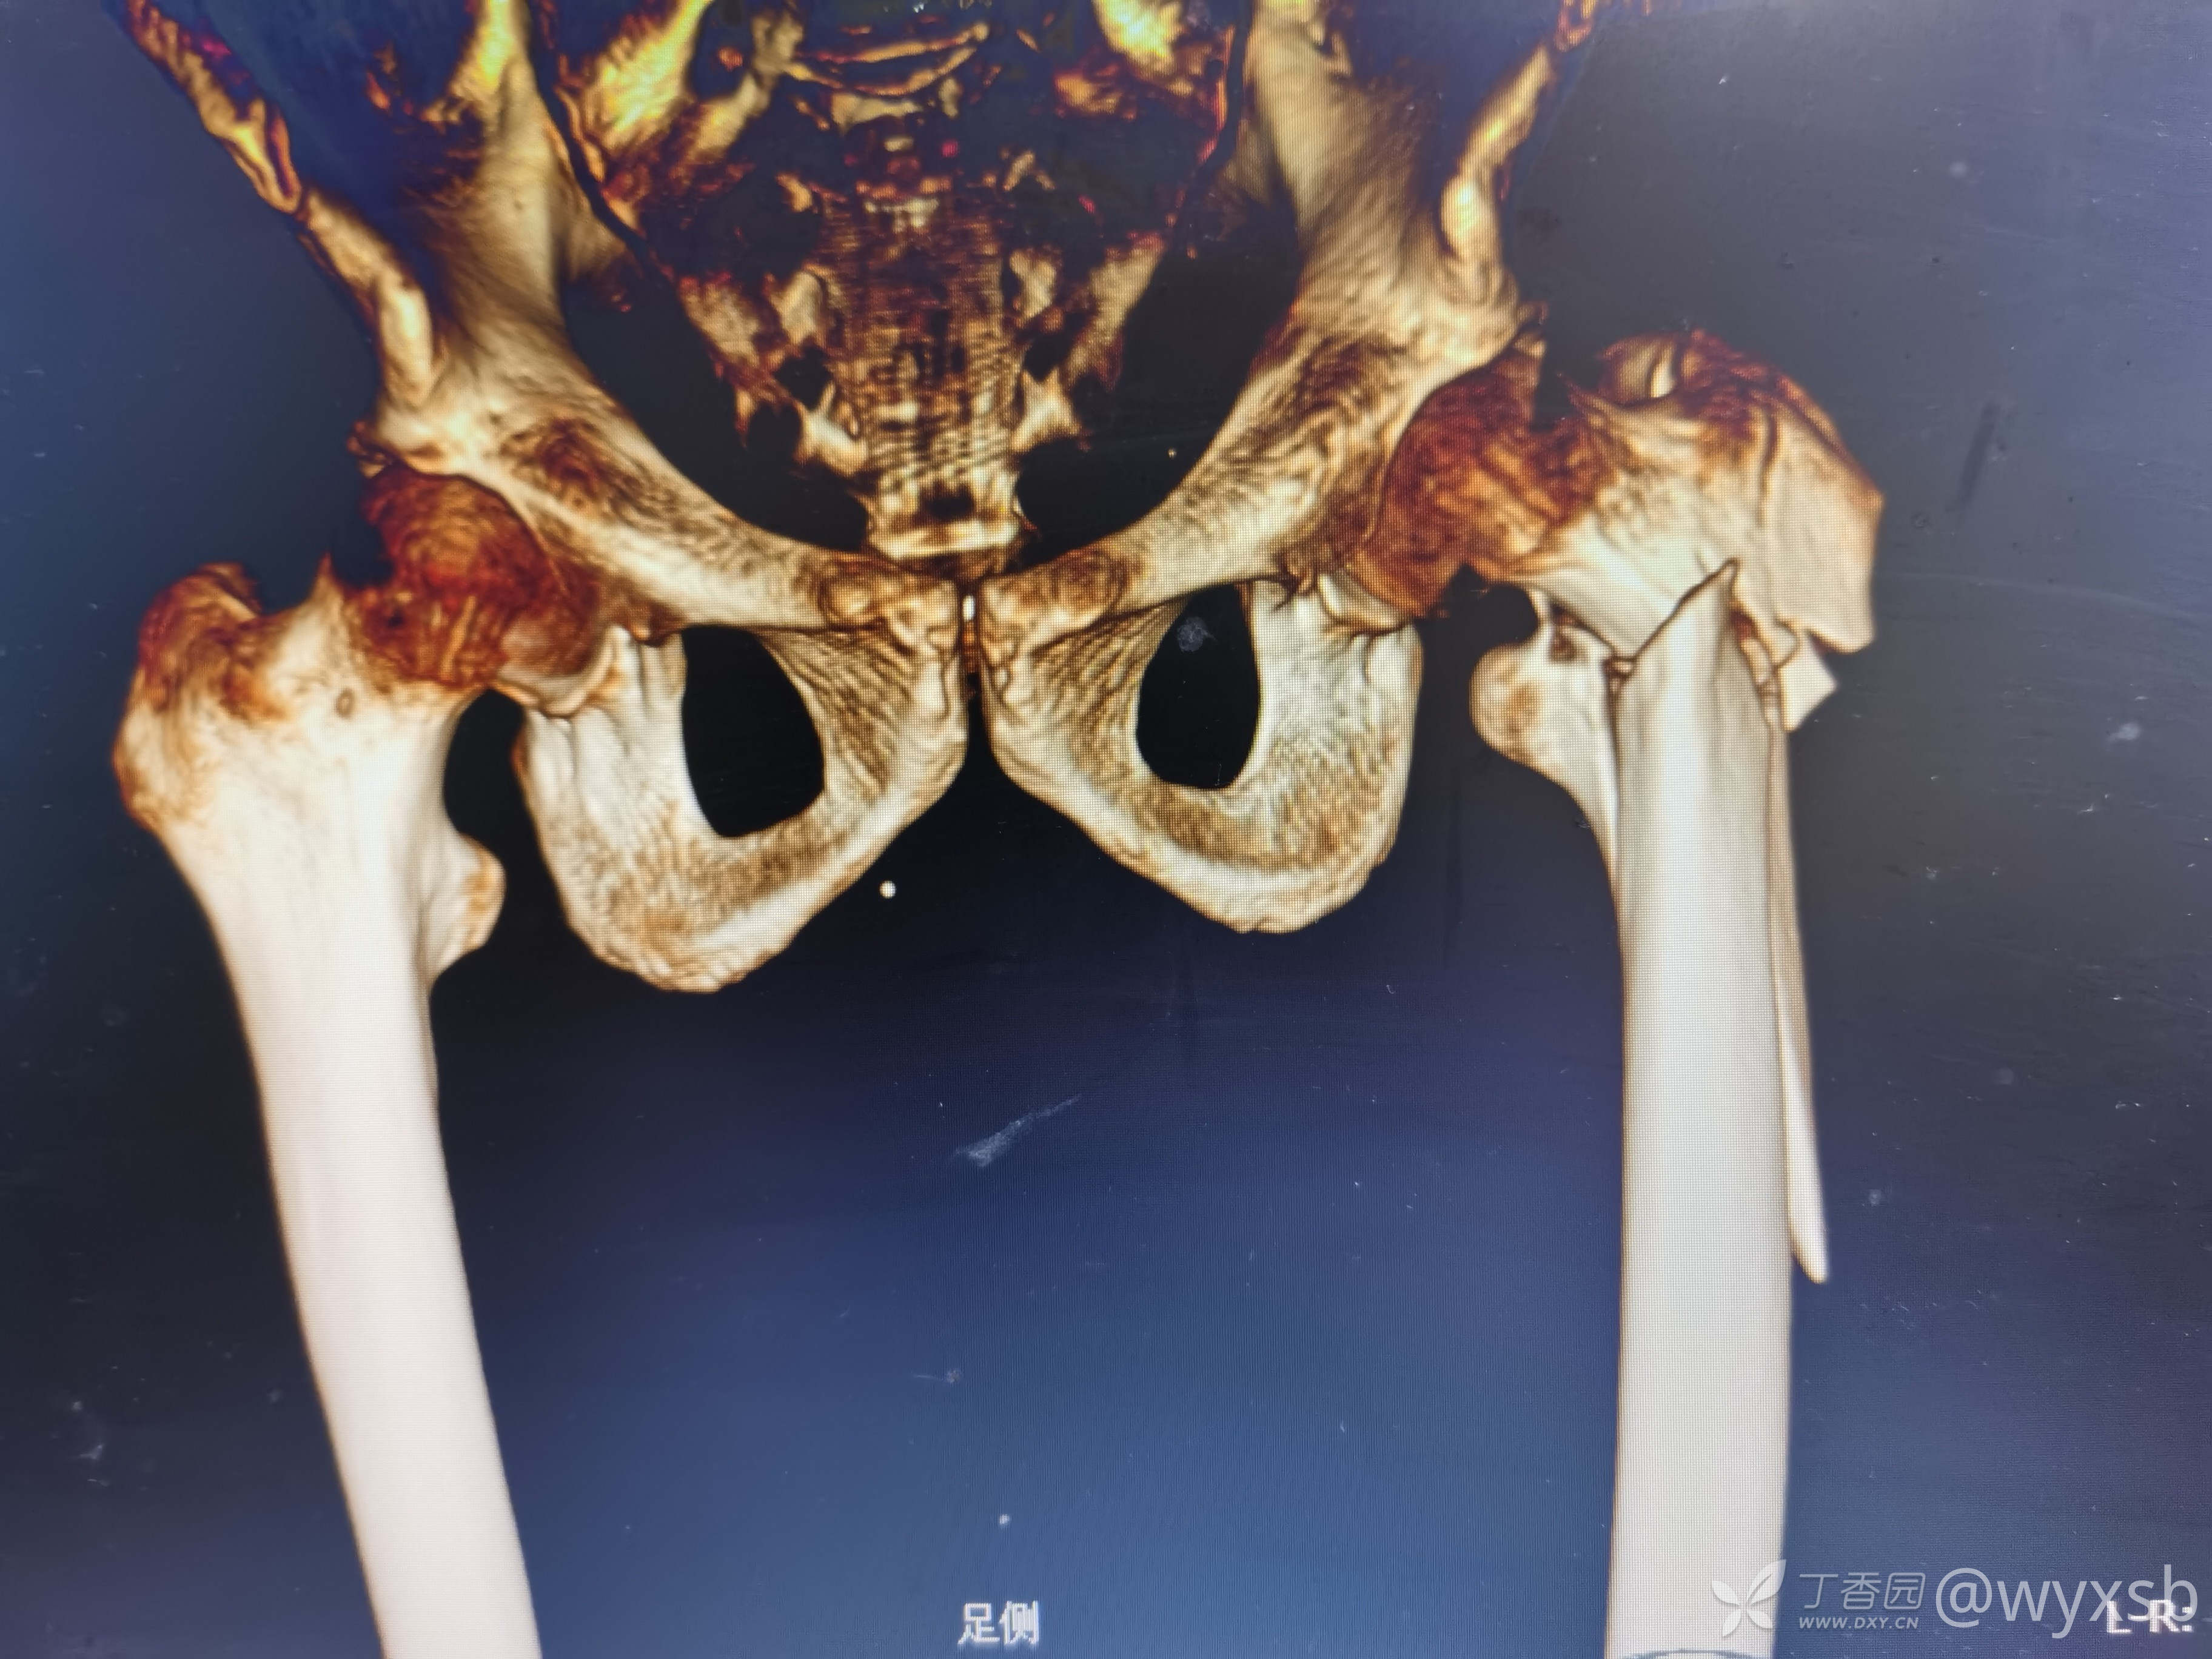

术前CT三维重建

术前重建